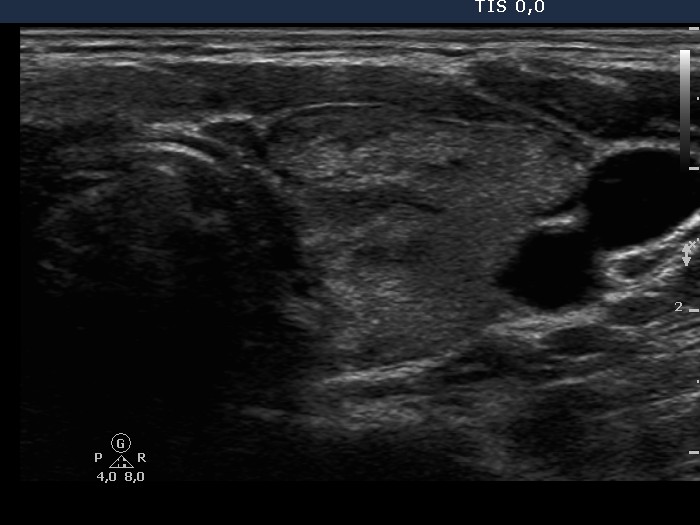

Follow-up investigation 32 months after first visit (ultrasonographic picture 4)

Patient 14 months after discontinuation of thyrostatic therapy in hyperthyroid state

Left lobe, transverse view. This lobe is minimally hypoechogenic.